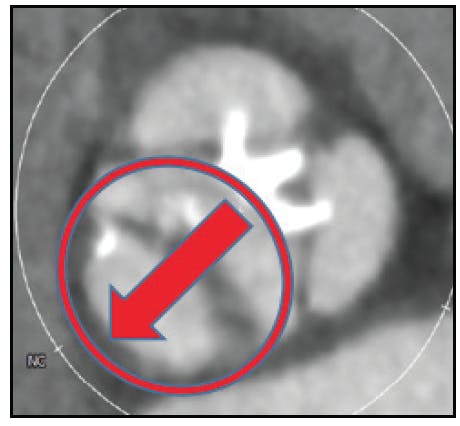

Heavy, asymmetric calcification patterns are also a particular concern in bicuspid valve disease. Heavy calcification may result in incomplete or asymmetric valve expansion and root injury, which can occur due to a contrecoup injury with balloon inflation and THV expansion (Figure 3). Balloon aortic valvuloplasty may be useful in this setting to judge the response of the calcified BAV anatomy before THV implantation. Self-expanding or mechanically expandable THV designs may also be advantageous, although further research on optimal THV selection is required. Unlike tricuspid aortic valves in which both coronary artery ostia are in the middle of the sinuses, in BAV anatomy, one or both ostia may be in proximity to the commissures (Figure 4). This, along with taller leaflet height and heavier calcification, may increase the risk of coronary obstruction, which also remains incompletely understood.

Figure 3. Examples of heavy, asymmetric calcification of BAV. Examples of heavy asymmetric calcification that can result in incomplete or asymmetric THV expansion and present a risk of aortic root injury through a contrecoup mechanism.